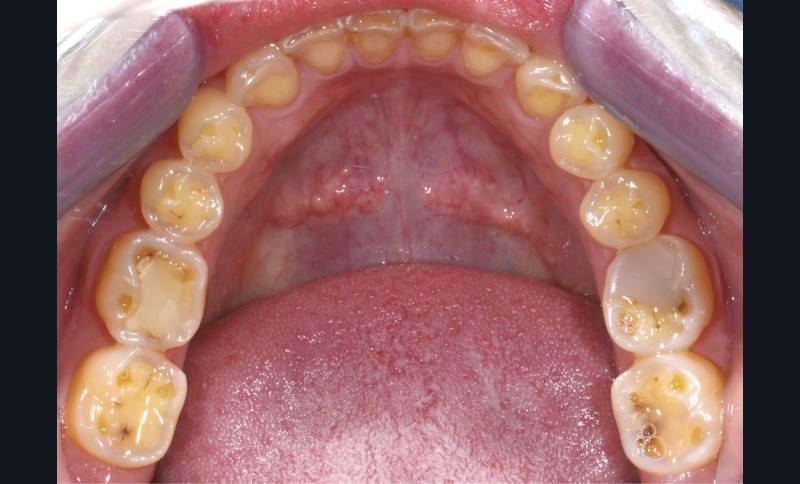

Une patiente âgée de 28 ans se présente en consultation avec une inquiétude au sujet de ses dents postérieures : elle a observé une usure avec un « jaunissement » des faces occlusales et se plaint de sensibilités répétées (fig. 1 à 3).

L’examen général met en évidence un bruxisme nocturne ainsi qu’une consommation peut-être excessive d’agrumes.

Les traitements qui ont été envisagés jusqu’à présent consistaient soit dans le port simple d’une gouttière nocturne, soit dans la réalisation de restaurations périphériques accompagnées de traitements endodontiques.